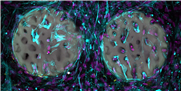

Um Knochen zu verbinden, werden heute harte steife Implantate verwendet (l.). Künftig könnten weiche Implantate aus einem Hydrogel eingesetzt werden. (Grafik: Xiao-Hua Qin / ETH Zürich)

Bisher haben die Forschenden das Material erst im Reagenzglas getestet. Dabei zeigte sich, dass knochenbildende Zellen das strukturierte Hydrogel rasch besiedeln und beginnen, Kollagen zu bilden, ein wichtiger Bestandteil des Knochens. Die Tests zeigten weiter, dass das Material biokompatibel ist und die knochenbildenden Zellen nicht schädigt. Die Forschenden haben das Basismaterial patentieren lassen und möchten es der medizinischen Industrie zugänglich machen.